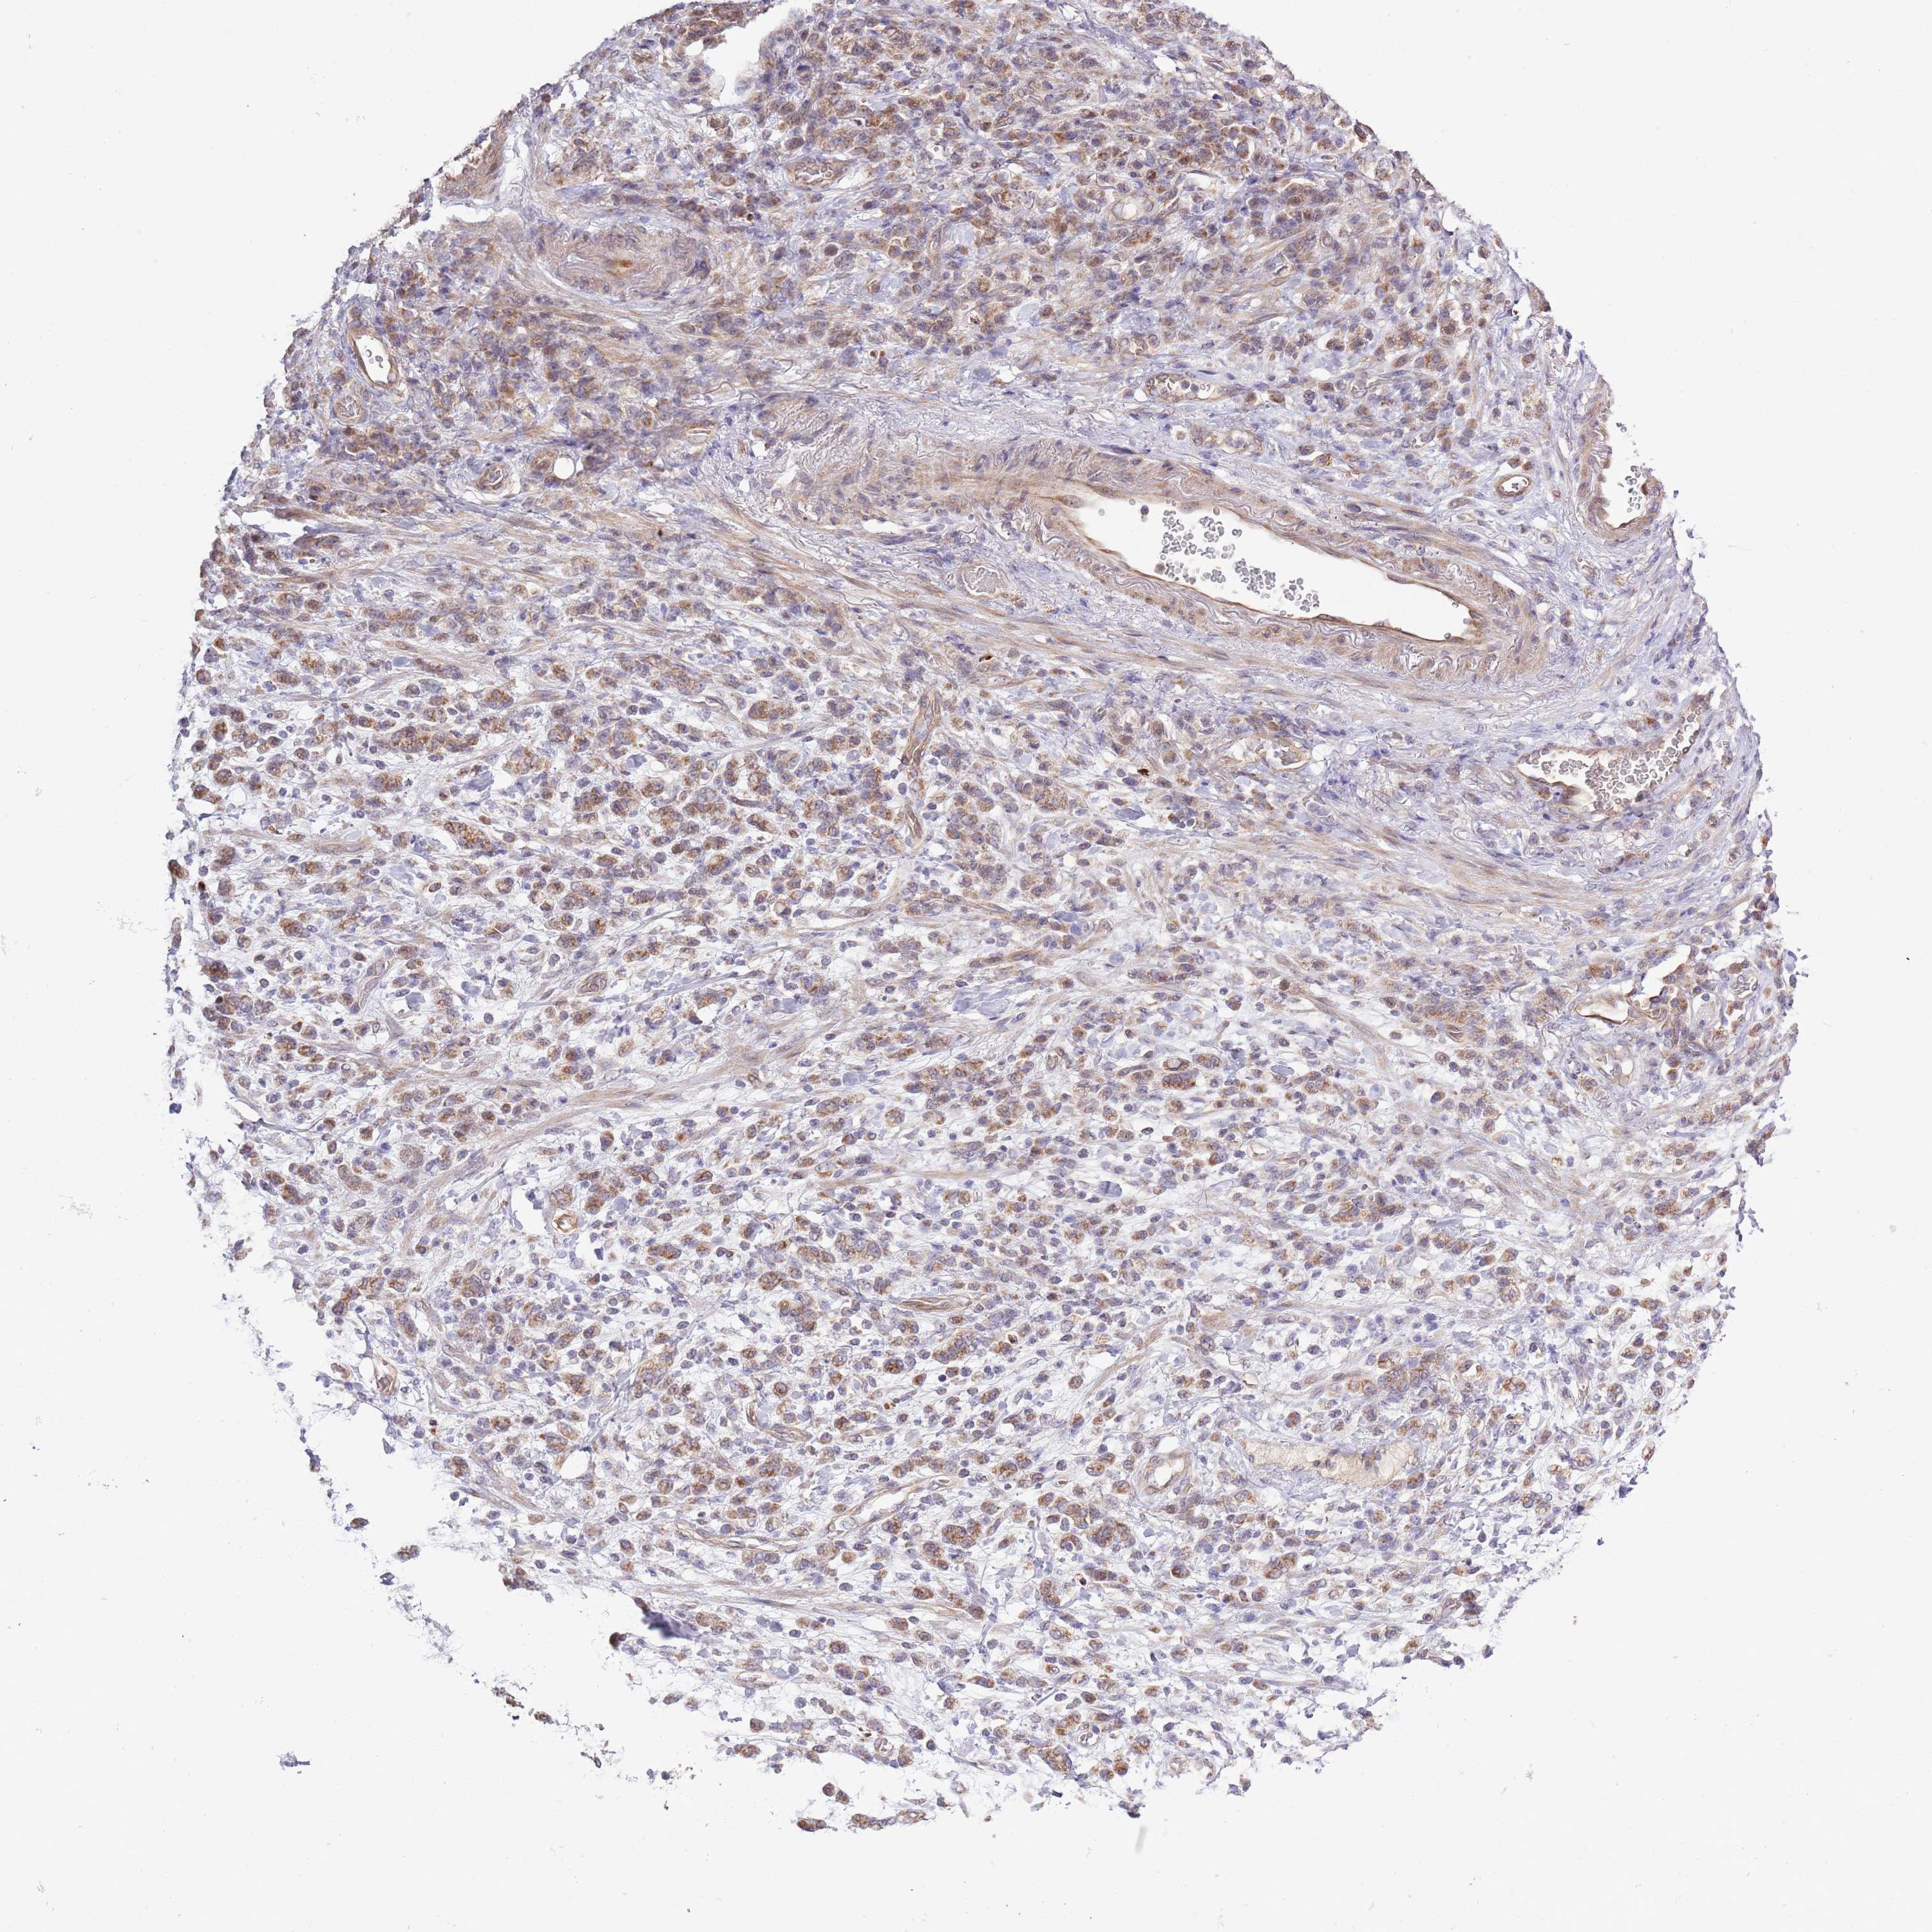

STOMACH CANCER - Protein expressioni

A mouse-over function shows sample information and annotation data. Click on an image to view it in a full screen mode. Samples can be filtered based on level of antibody staining by selecting one or several of the following categories: high, medium, low and not detected. The assay and annotation is described here.

Note that samples used for immunohistochemistry by the Human Protein Atlas do not correspond to samples in the TCGA dataset.

Antibody stainingi

Antibody staining in the annotated cell types in the current human tissue is reported as not detected, low, medium, or high, based on conventional immunohistochemistry profiling in selected tissues. This score is based on the combination of the staining intensity and fraction of stained cells.

Each image is clickable and will lead to virtual microscopy that enables deeper exploration of all samples and also displays staining intensity scores, fraction scores and subcellular localization as well as patient and tissue information for each sample.

Antibody HPA041391

Antibody HPA044250

Staining

High

Medium

Low

Not detected

Intensity

Strong

Moderate

Weak

Negative

Quantity

>75%

75%-25%

<25%

None

Location

Nuclear

Cytoplasmic/membranous

Cytoplasmic/membranous,nuclear

Adenocarcinoma, NOS

Adenocarcinoma, High grade